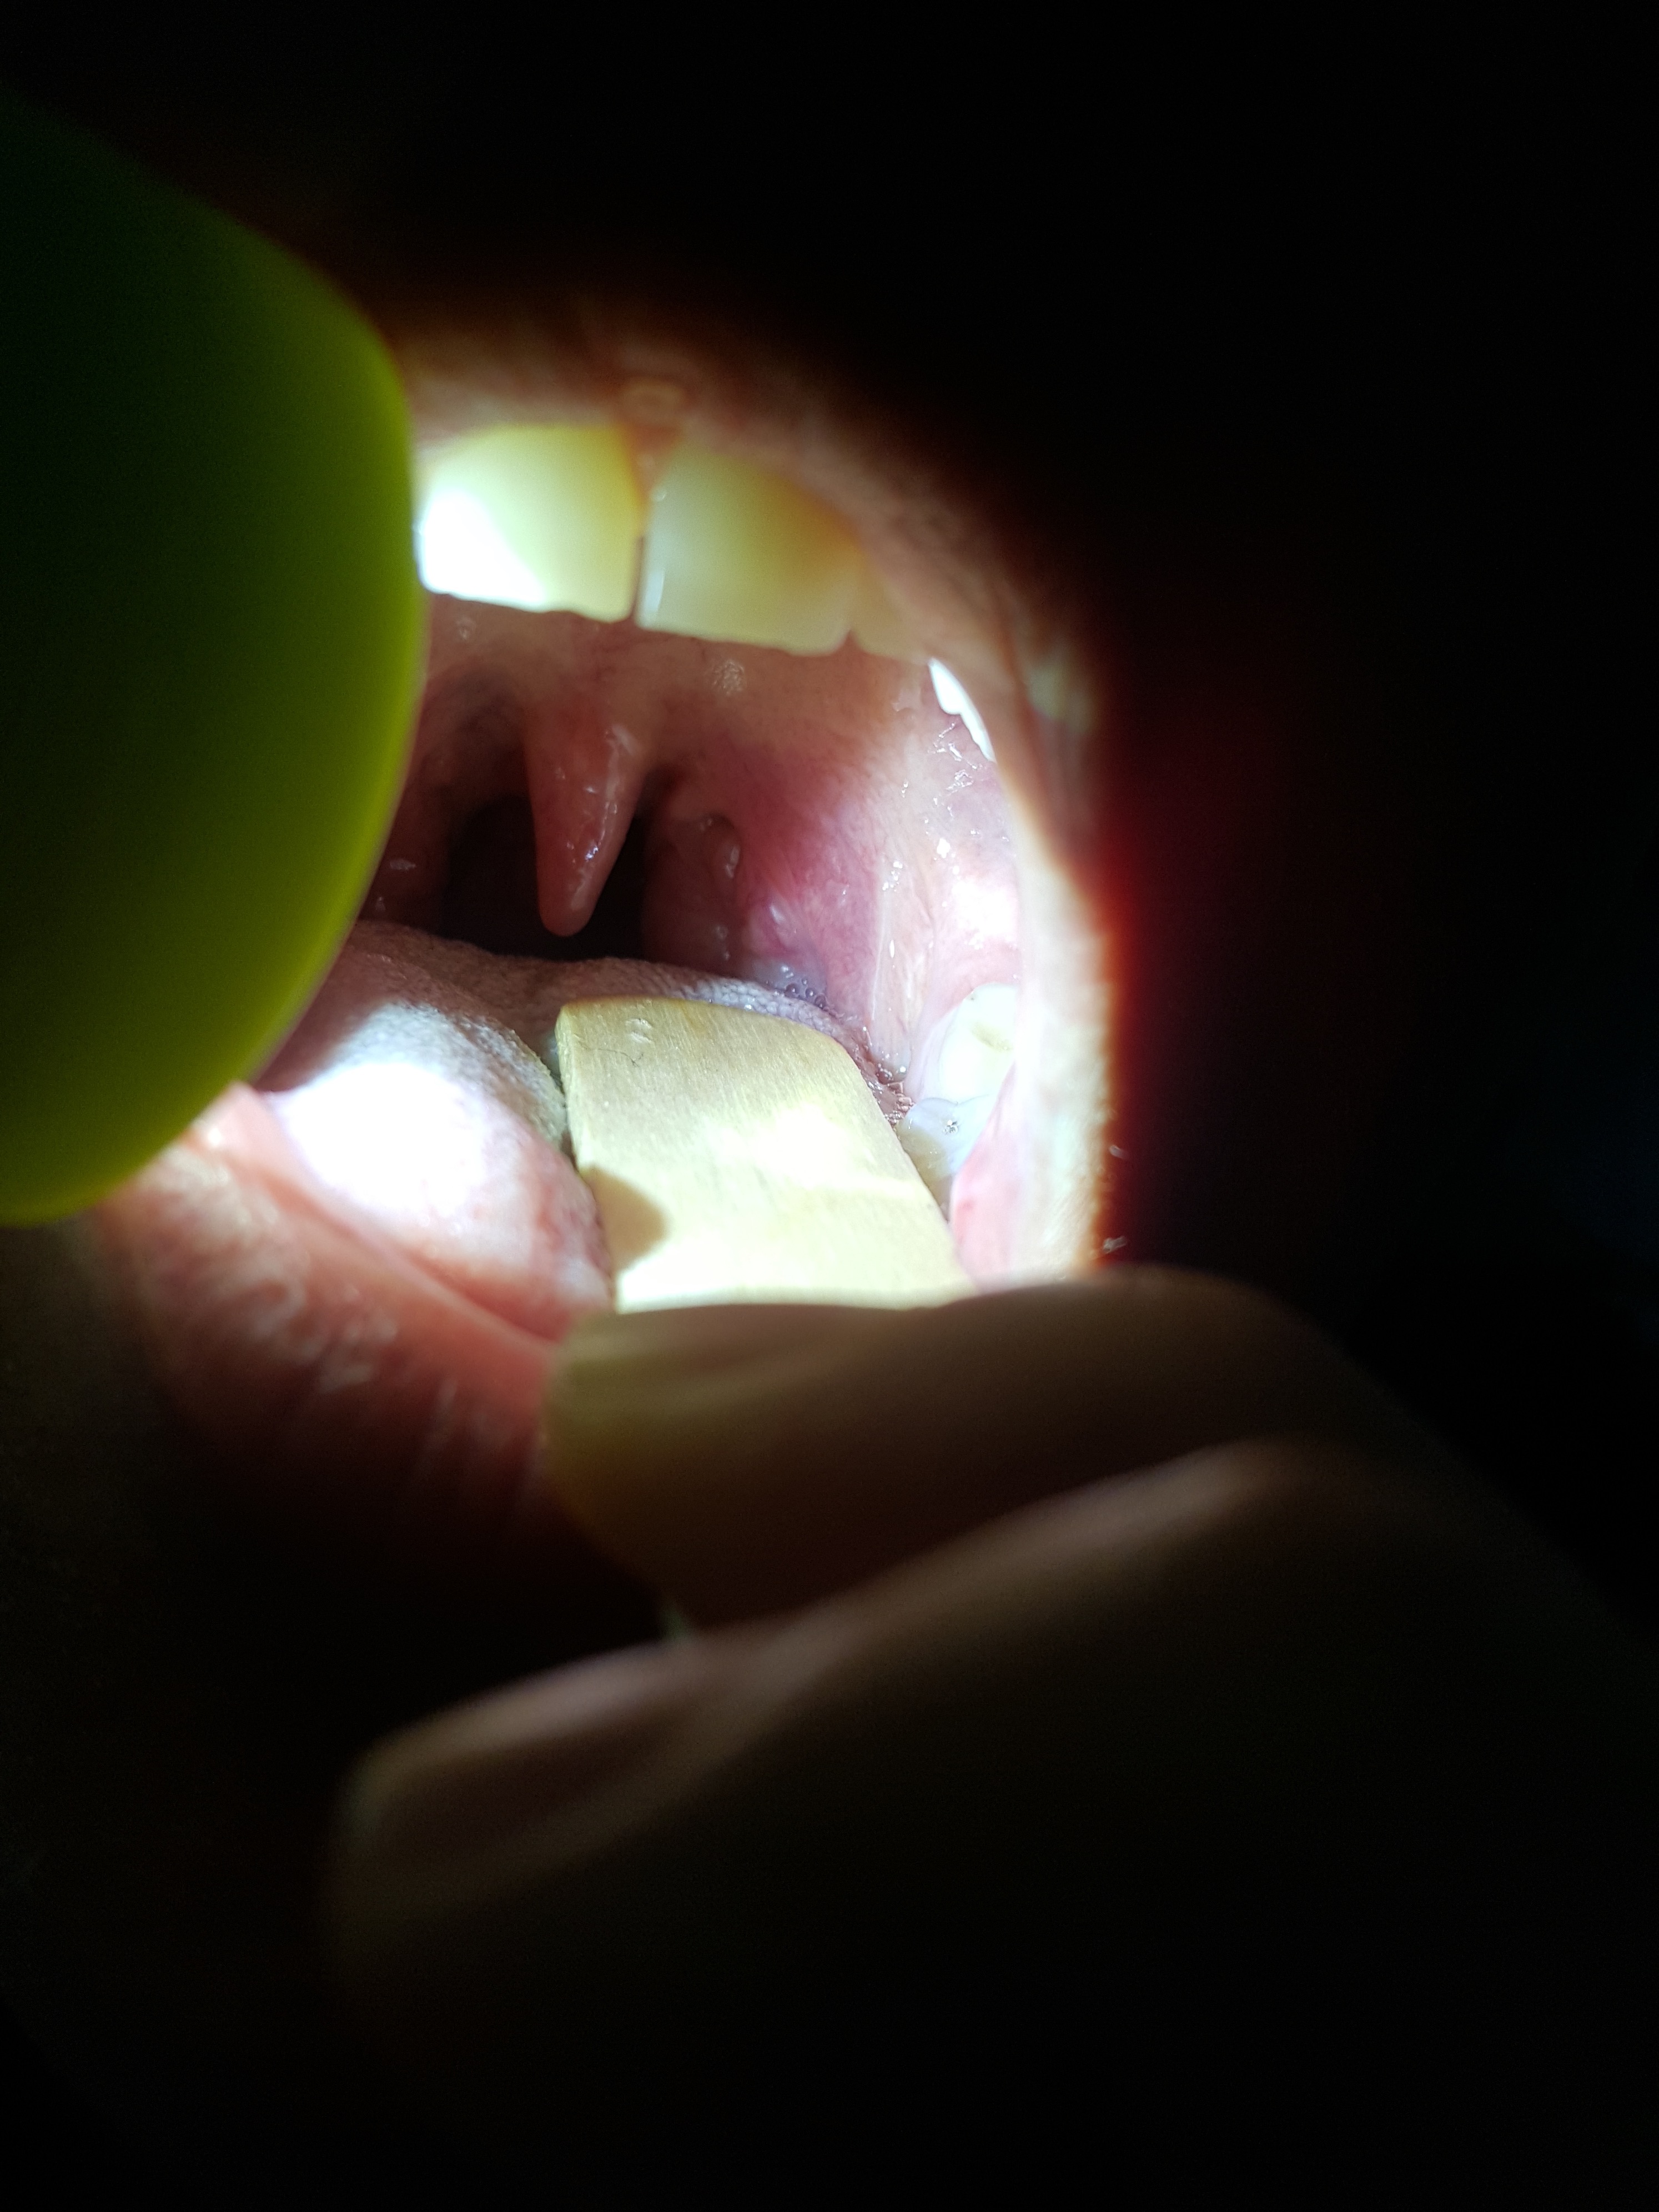

20160623_145633 Published August 20, 2016 at 2988 × 3984 in Healing Experiment: Peritonsillar abscess (Qunisy) & Cool Stuff It Showed Me About God My throat on the day after it felt better, I hadn’t thought to photograph it till then. At it’s worst it was pushing the hanging down thingy in the middle on a 45 degree angle to the other side